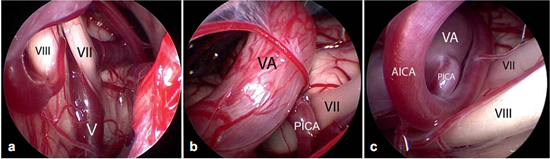

Figure 6不同类型的血管压迫。Ⅶ=面神经;Ⅷ=蜗神经

a:由靠近脑干的静脉(Ⅴ)所造成的压迫;

b:椎动脉(VA)和小脑右下动脉(PICA)共同压迫;

c:椎动脉(VA)、下移的小脑右下动脉(PICA)和小脑前下动脉(AICA)共同压迫。